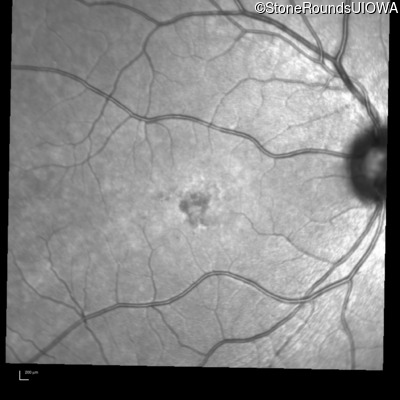

Age at visit: 17 years

OD OS

This 17 year old female first noted problems with her visual acuity around age 13 when she had trouble seeing the projector from the back of the classroom.